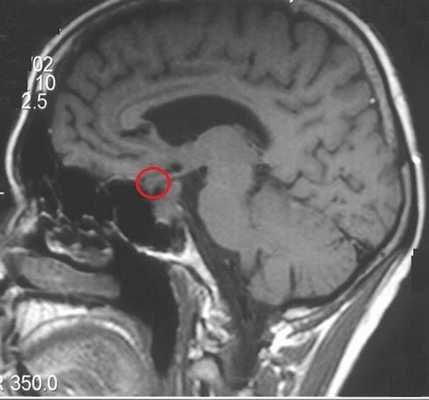

Поскольку диагностировать микроаденому по клиническим симптомам сложно, ее визуализация возможна только с помощью магнитно-резонансной томографии. Признаками микроаденомы на МРТ станут:

- При нативном сканировании в отделах аденогипофиза определяется зона гипоинтенсивного МР-сигнала на Т1-ВИ, округлой формы, с четкими, неровными контурами.

- После внутривенного введения парамагнитного контрастного препарата контрастное усиление выражено неравномерно, определяется равномерное накопление контрастного препарата неизмененной тканью гипофиза с задержкой контрастирования от выявленного участка в аденогипофизе.